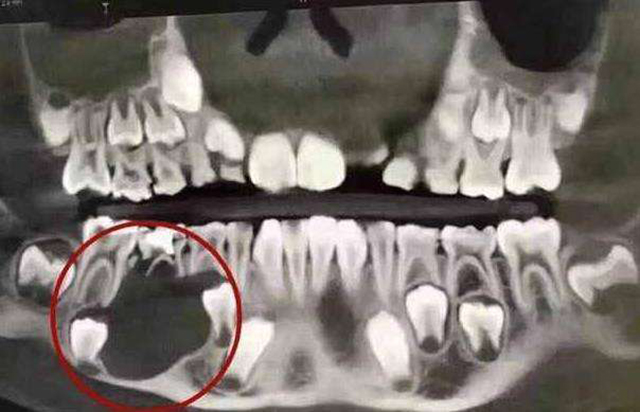

“反正乳牙都会掉,坏了等到它长出来新的就行了呗”,这应该是不少妈妈的想法。但是乳牙龋齿绝不只是疼、不美观等的危害。

乳牙龋齿如果太严重,不及时的进行治疗,造成的危害还会波及到恒牙。导致恒牙的硬组织发育不完全,出牙顺序紊乱,造成牙齿参差不齐。